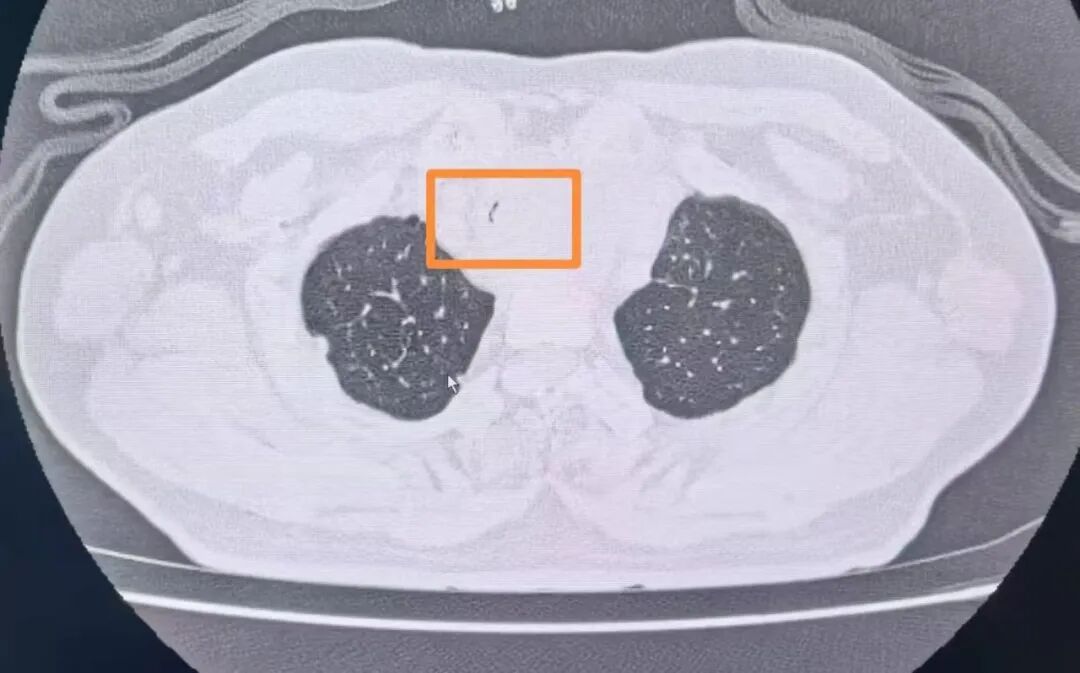

經(jīng)復(fù)查胸部CT發(fā)現(xiàn)患者氣管已經(jīng)出現(xiàn)明顯狹窄,內(nèi)徑最窄處直徑不到2mm(正常成年男性氣管內(nèi)徑為18-22mm),呈“一線天”樣改變,整個氣管僅靠一條細微的縫隙維持著少量的通氣,意味著病人隨時有發(fā)生窒息的危險。甲乳外科立即組織開展了多學(xué)科討論。經(jīng)過對病情的充分分析,呼吸與危重癥醫(yī)學(xué)科副主任陳暉建議緊急行氣管內(nèi)支架置入術(shù)解除大氣道梗阻。